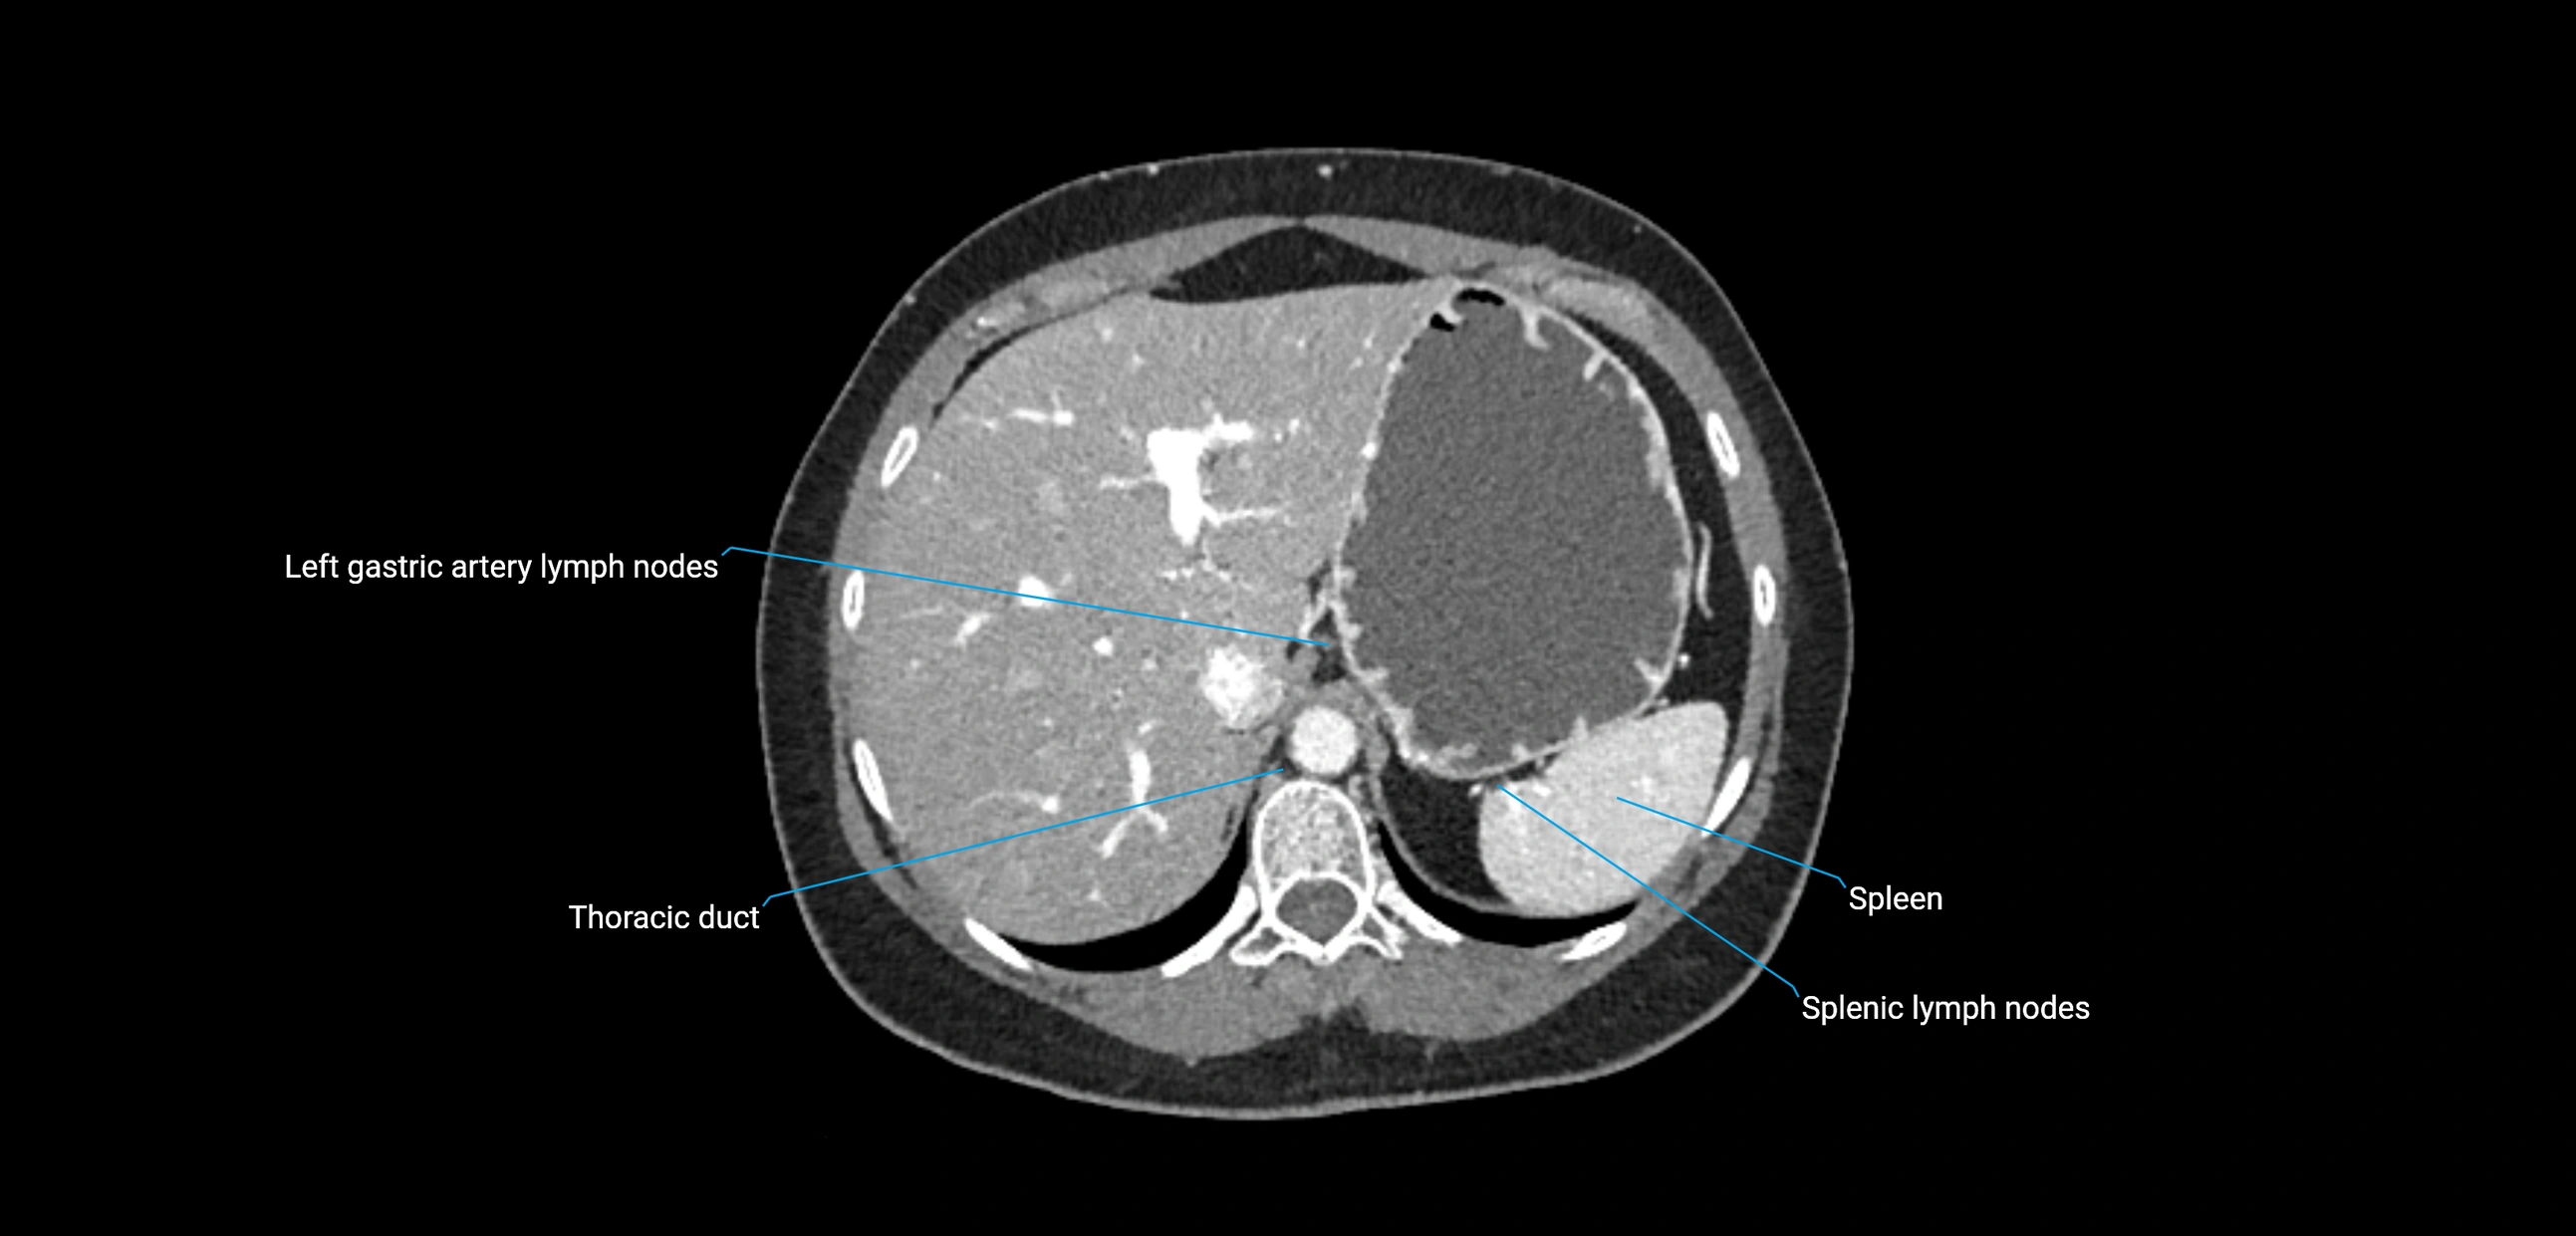

CT Appearance

CT Pre-Contrast:

• Nodes appear as soft-tissue density nodules adjacent to the aorta and IVC

• Calcification may be seen in chronic infections (e.g., tuberculosis)

CT Post-Contrast:

• Normal nodes enhance homogeneously

• Malignant nodes may show heterogeneous enhancement, central necrosis, or conglomerate formation

• Size >1 cm short axis is suspicious, though morphology and distribution are equally important

CT image

image